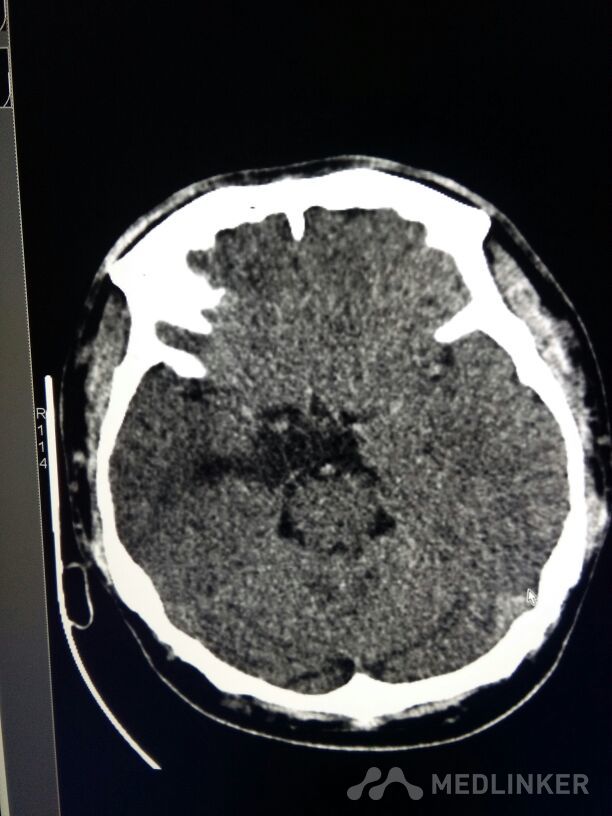

考虑表皮样囊肿?

表皮样囊肿